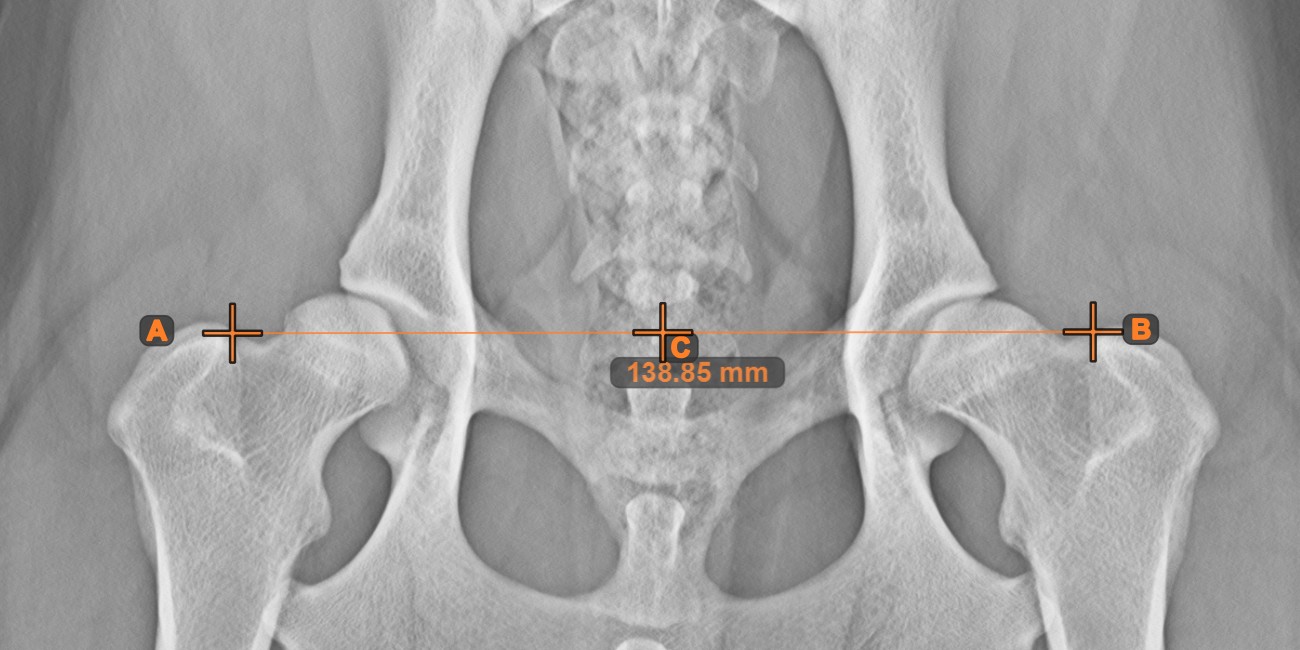

Line Measurement

Create a line measurement to calculate the distance between two points with high precision.

Select the Line Measurement tool and assign it to one of the available mouse buttons. Place the start and end points on the scene or select them from already existing points on the image. The distance between the two points will be automatically calculated by using the default calibration data, or the recalibrated data by the length calibration measurement.

Modify the start and end point by using the Select/Move Item tool. The distance between the two points will be automatically recalculated.

../_images/image164.jpg

Center Point of Line

Identify and mark the center point of a new or existing line measurement on the scene by using the Center Point of Line tool.

Select the tool from the left toolbar and assign it to one of the available mouse buttons. Place the start and end points on the scene, select them from already existing points on the image, or select an already drawn line from the scene. The center point of the line will be automatically calculated and placed on the scene. The center point of each line will always be marked with the letter C.

../_images/image284.jpg